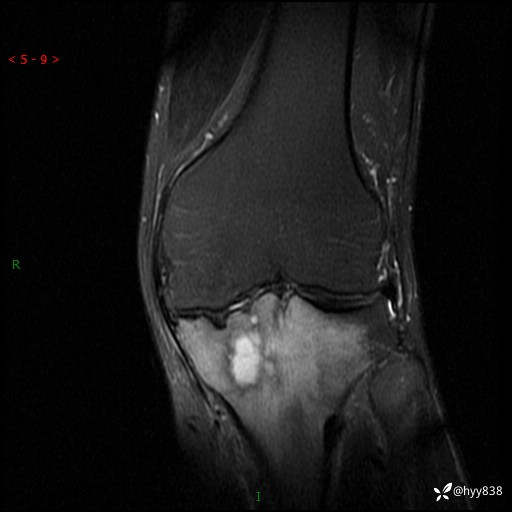

cor T2WIfs

干骺端溶骨性病变病灶周广泛水肿